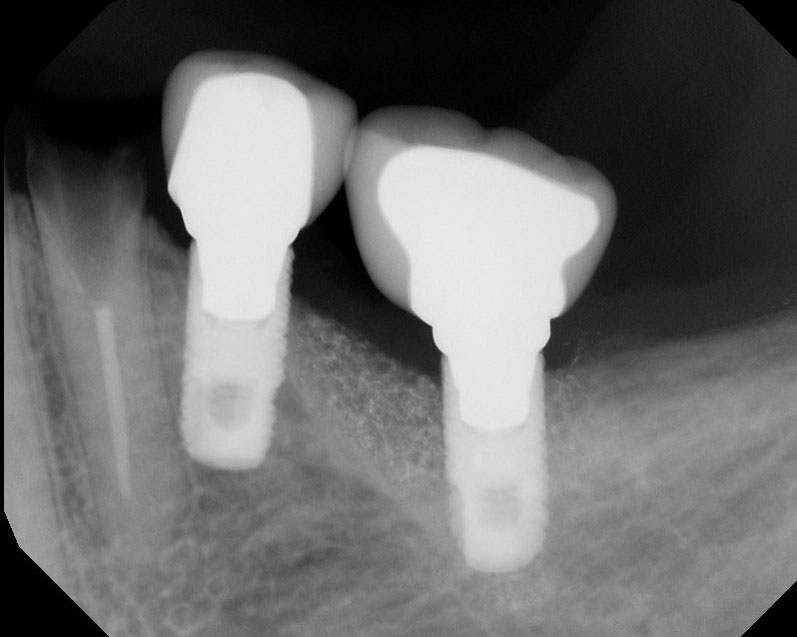

Implants

This treatment involves implanting artificial dental roots, and restoring dental crown without damaging the adjacent teeth.